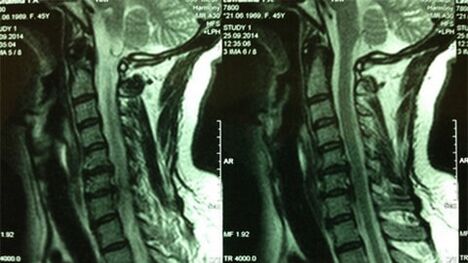

- X -Ray of the cervix department;In the initial phase of the process, the MRI of the cervical department will be more informative - it will ensure a high visualization of solid and soft tissue - shows the condition of the intervertebral discs, the presence of osteophytes, deformations, damage to the nerve roots and blood vessels;evaluates the condition of the ligaments, muscles, bone tissue;